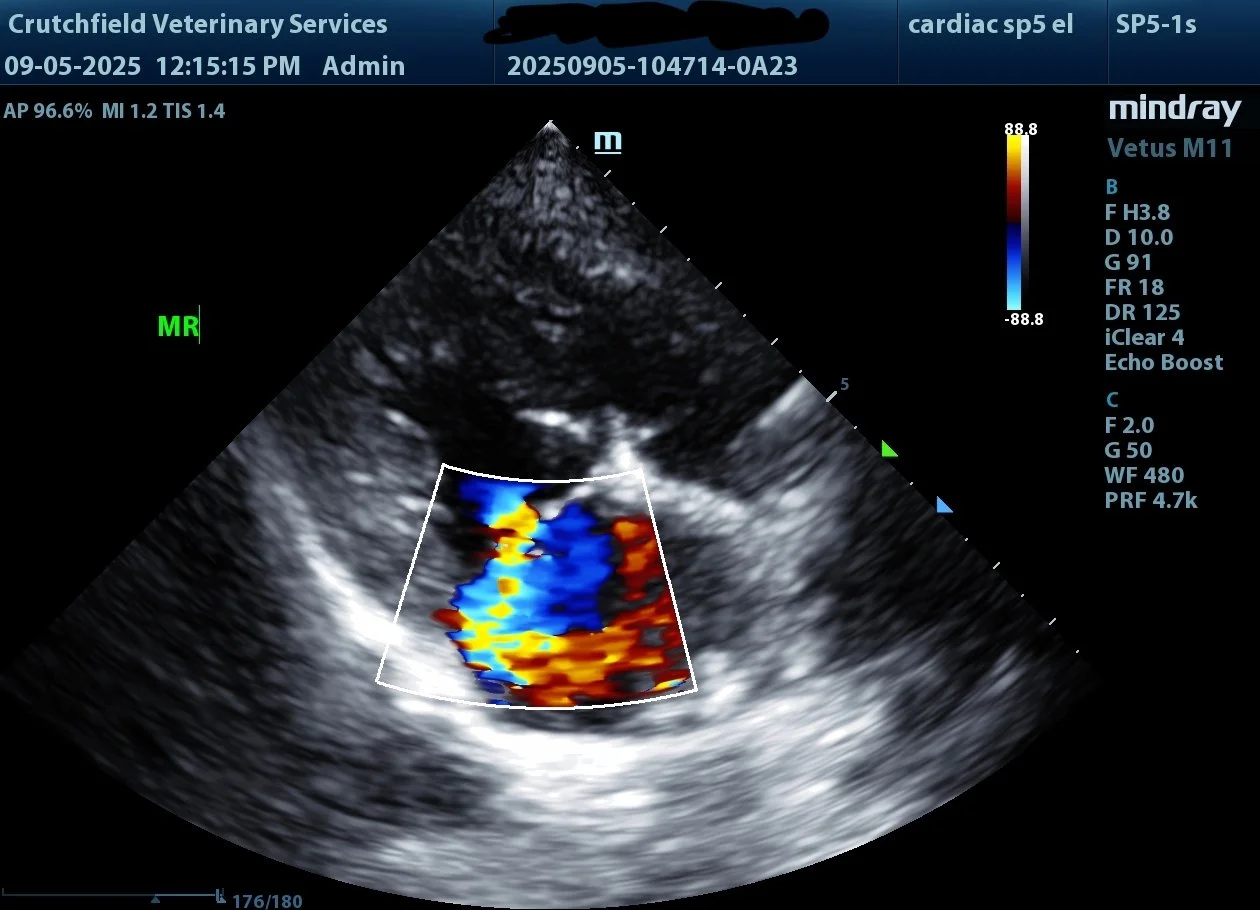

Dr. Crutchfield performs ultrasound exams on dogs and cats by appointment only. Please call, text or email to schedule your pet’s ultrasound.